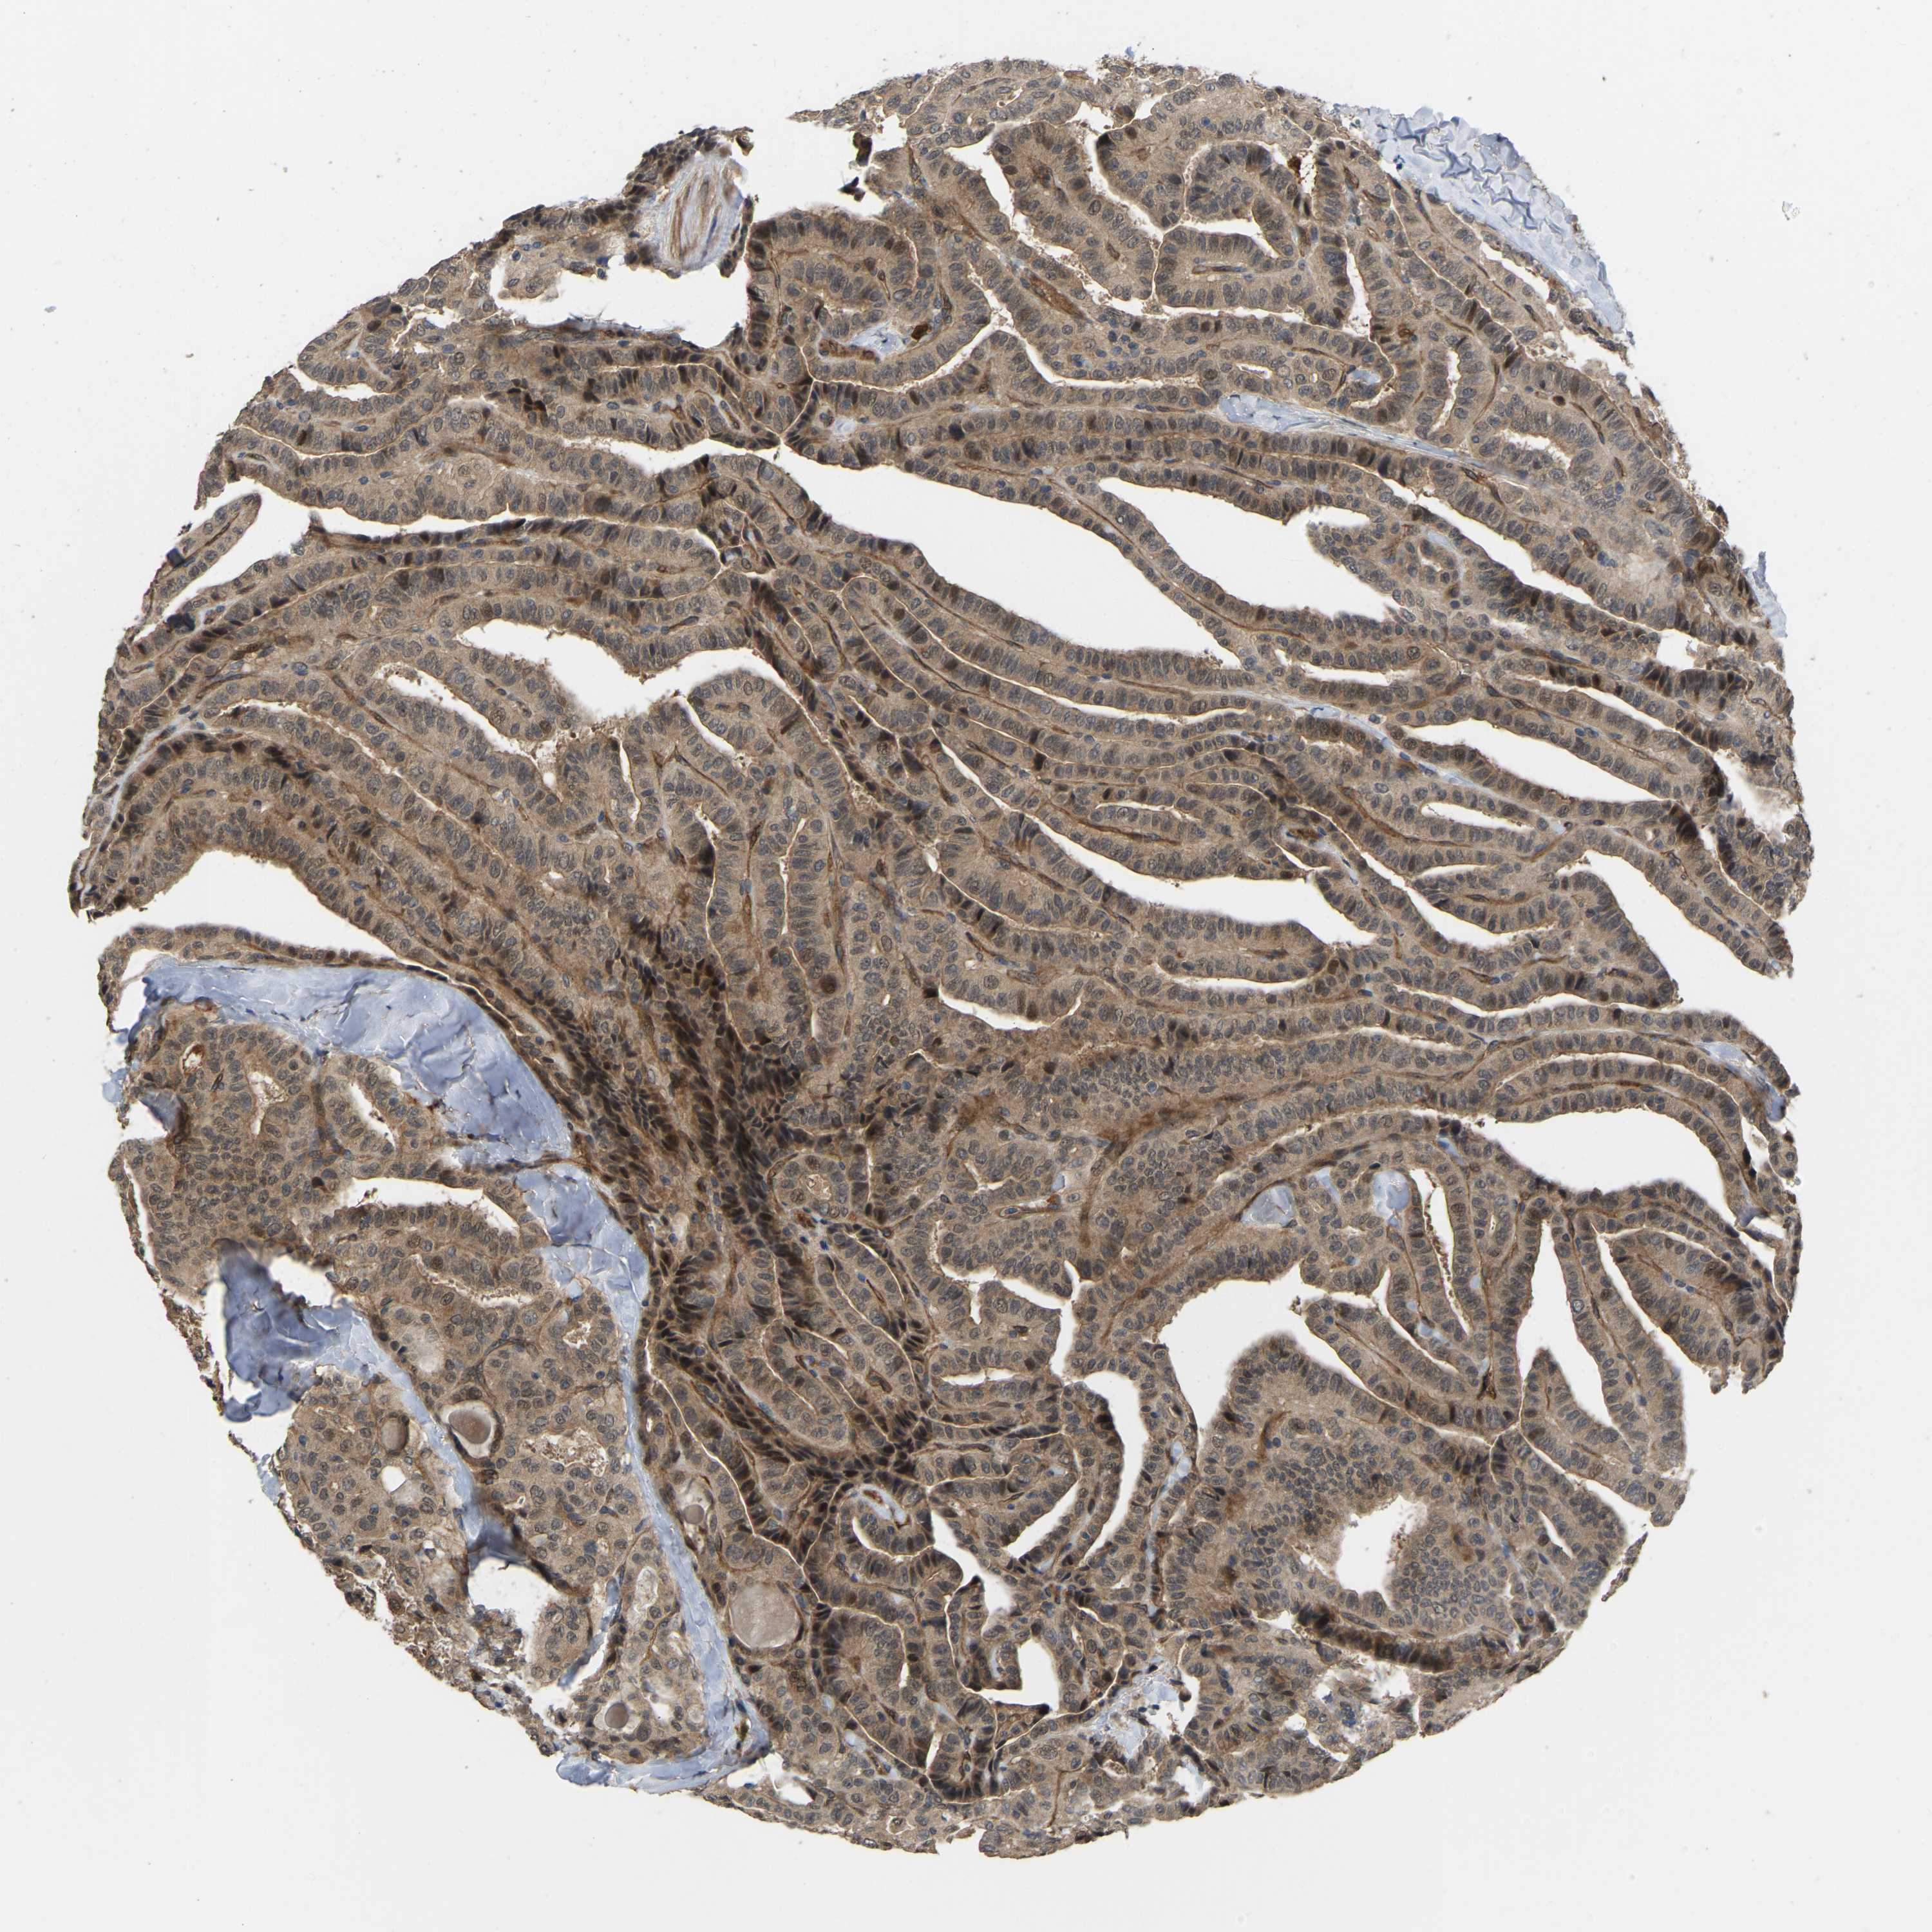

THYROID CANCER - Protein expressioni

A mouse-over function shows sample information and annotation data. Click on an image to view it in a full screen mode. Samples can be filtered based on level of antibody staining by selecting one or several of the following categories: high, medium, low and not detected. The assay and annotation is described here.

Note that samples used for immunohistochemistry by the Human Protein Atlas do not correspond to samples in the TCGA dataset.

Antibody stainingi

Antibody staining in the annotated cell types in the current human tissue is reported as not detected, low, medium, or high, based on conventional immunohistochemistry profiling in selected tissues. This score is based on the combination of the staining intensity and fraction of stained cells.

Each image is clickable and will lead to virtual microscopy that enables deeper exploration of all samples and also displays staining intensity scores, fraction scores and subcellular localization as well as patient and tissue information for each sample.

Antibody HPA008183

Antibody HPA053882

Antibody CAB019313

Staining

High

Medium

Low

Not detected

Intensity

Strong

Moderate

Weak

Negative

Quantity

>75%

75%-25%

<25%

None

Location

Nuclear

Cytoplasmic/membranous

Cytoplasmic/membranous,nuclear

Papillary adenocarcinoma, NOS

Follicular adenoma carcinoma, NOS